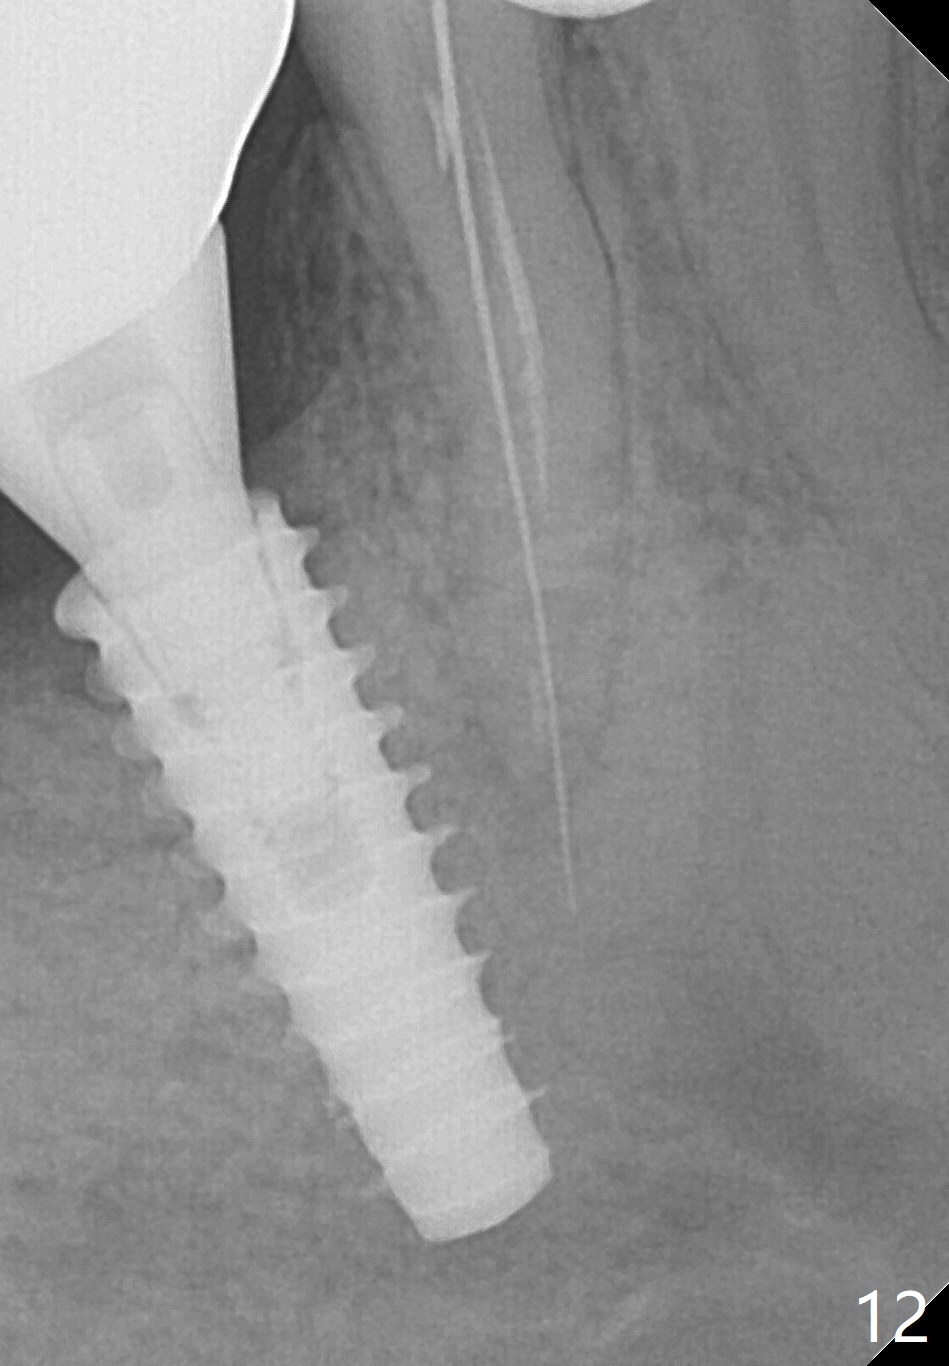

Bone graft seems to sink down and becomes denser 3 months postop (Fig.6 arrow). The bone continues being denser 5 months postop (Fig.7). There is periapical radiolucency of the tooth #29 (^). RCT is done (Fig.8). The pain persists 2 weeks postop (Fig.9,10). There is no missing canal (Fig.9). The apex is close to the implant (Fig.9 *). Apicoectomy will be performed if needed. It appears that the implant is also placed buccal (Fig.10 <) and/or the implant too large for the site. Therefore there should be a 2-3 mm buccal gap before and after implant placement. Separation and reflection of the buccal flap allows better visibility. The pain persists 1 month post RCT and 6 months post implant placement. RCT retreatment is initiated (Fig.11,12) with placement of Calcium Hydroxide paste after redebridement with 30/.04 rotary file at 23.5 mm (.5 mm longer than the earlier RCT, Fig.13). RCT retreatment finishes with apparent transportation and extrusion in 4 weeks (Fig.14,15), followed by apicoetomy (Fig.16,17) (20 days later)). Discomfort remains 2.5 months postop (Fig.18). Keep watching.